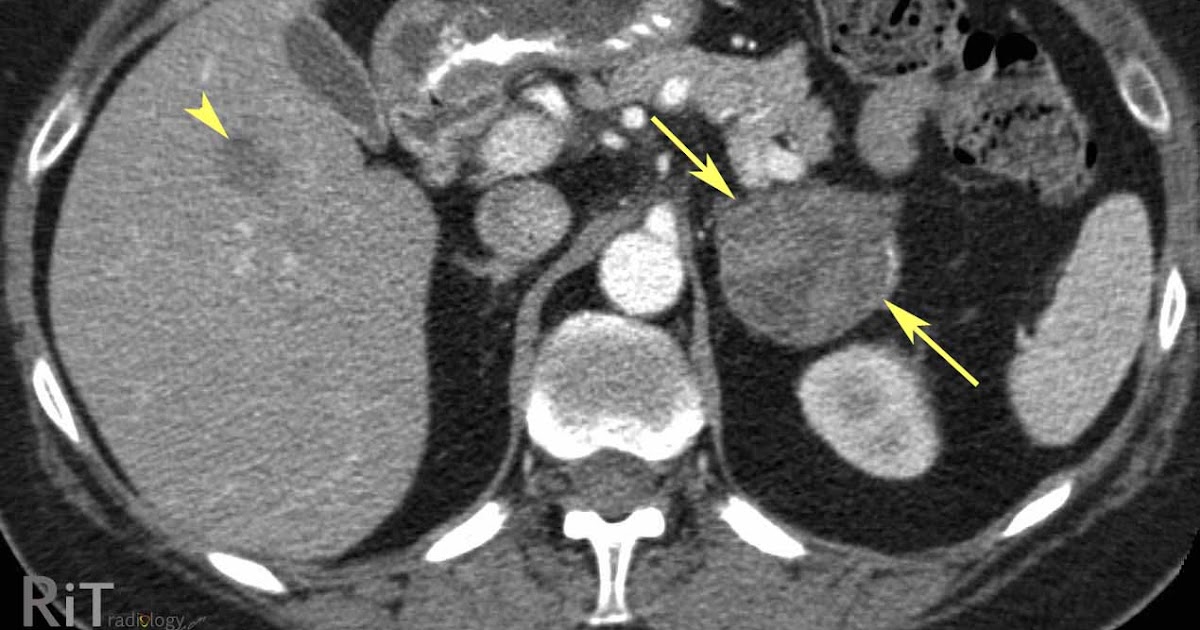

From radiologyinthai.blogspot.com

RiT radiology Adrenal Cortical Carcinoma Adrenal Cortical Cancer Stage 2  But it's most likely to affect children. Doctors divide adrenocortical carcinoma into four stages,.  treatment of adrenal cancer depends to a large degree on where the cancer started and how far it has spread.   adrenocortical carcinoma (also called acc or adrenal cancer) treatment usually involves surgery and may include.   adrenal cancer, also called adrenocortical cancer, can occur. Adrenal Cortical Cancer Stage 2.